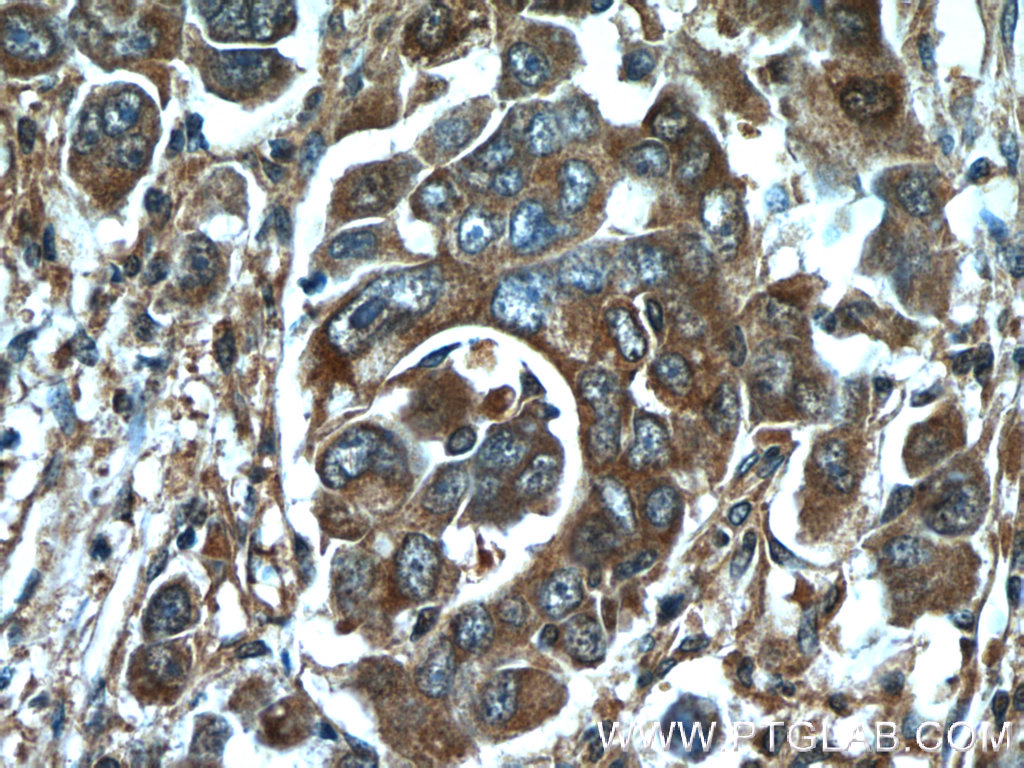

HMGCR抗体

产品名称: HMGCR抗体

英文名称: HMGCRAntibody

产品编号: XY13533-1

使用范围: WB,ELISA,IHC-P,IHC-F,IF

HMGCR抗体